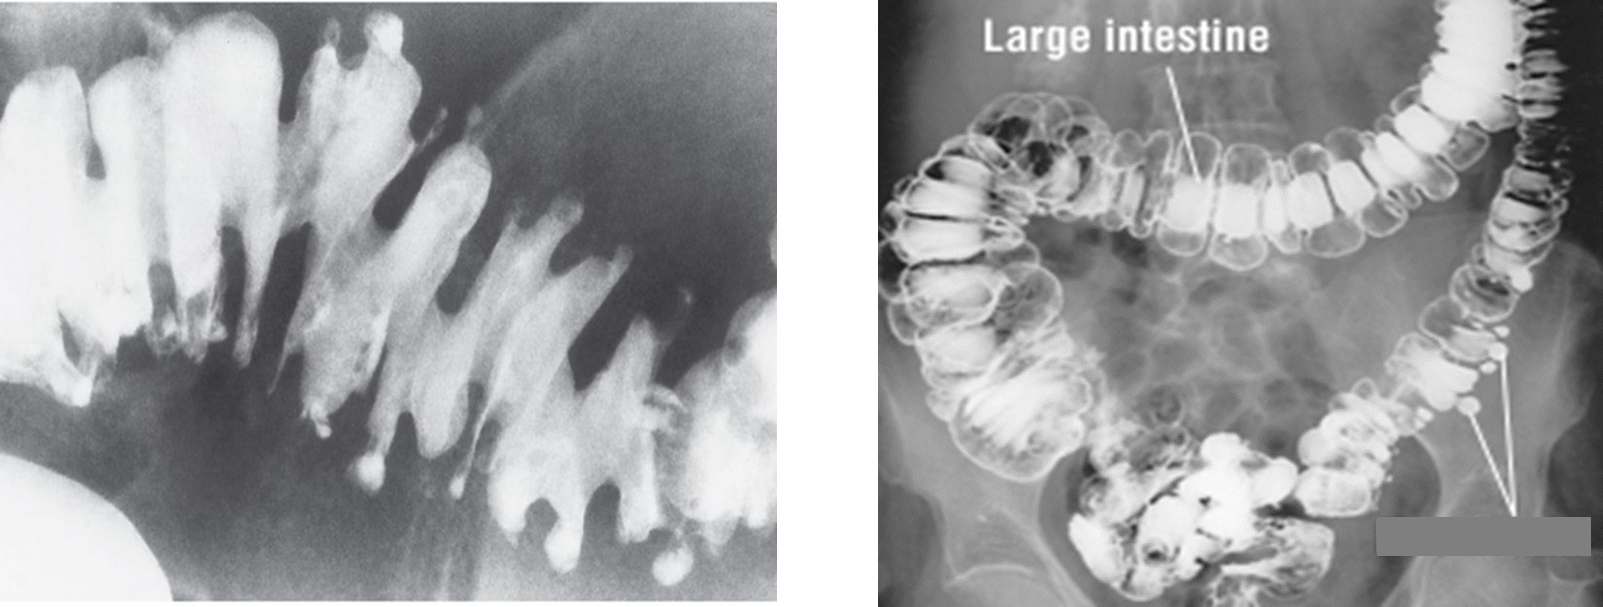

Wavy border, thickening folds

Appear as round or oval filling defects (beads

Large Bowel Obstruction

About 70% of this bowel obstruction result from primary colonic carcinoma.

Diverticulitis and volvulus account for most other cases.

Coiled-spring appearance of barium trapped between the intussusceptum and surrounding bowel.

A bowel obstruction (and therefore air-fluid levels and bowel dilation) proximal to it. There may be an absence of gas in the distal collapsed bowel.

Radiological Appearance:

Skip lesions, in severe cases it resembles a cobblestone appearance

Radiological Appearance:

Double contrast barium enema of early __ show fine granularity of the mucosa.

Double contrast barium enema of chronic __ show a Lead pipe sign (colon). The diseased segment of the colon exhibits a complete loss of pouch markings, resulting in a smooth-walled, cylindrical appearance.

Radiological Appearance:

Apple core sign

Radiological Appearance:

Saw-toothed appearance